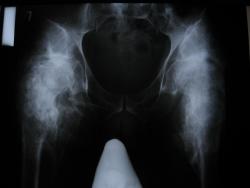

Последствия ПСМТ(04.08.04). Спастический грубый тетрапарез до плегии слева. Массивные гетеротопические оссификаты обоих тазобедренных сусвтавов, в следствии нейро-трофических нарушений. До травмы пациент был абсолютно здоров.

Наверное, это можно назвать нейрогенной остеоартропатией. Красивая картинка.

Что касается картинки: КАРТИНКА действительно красивая :)